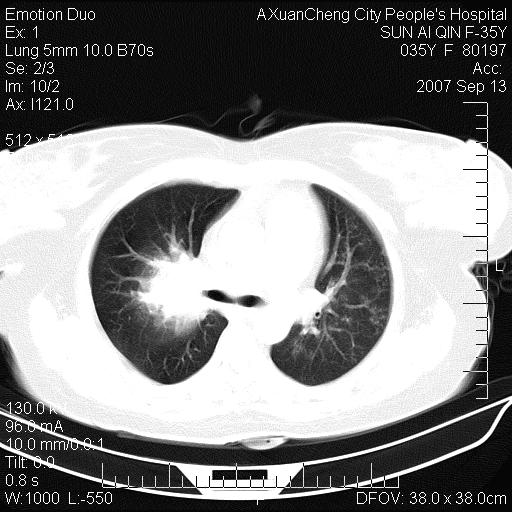

以下是引用天南地北在2007-9-13 13:43:00的发言:[br]考虑双肺、肺门侵润

以下是引用ydx_74在2007-9-13 15:42:00的发言:[br]仅看片,考虑右上肺癌并双肺转移,结合病史,考虑肺门、肺内淋巴侵润

以下是引用同在2007-9-13 15:08:00的发言:[br]支持肺门及双肺侵润.